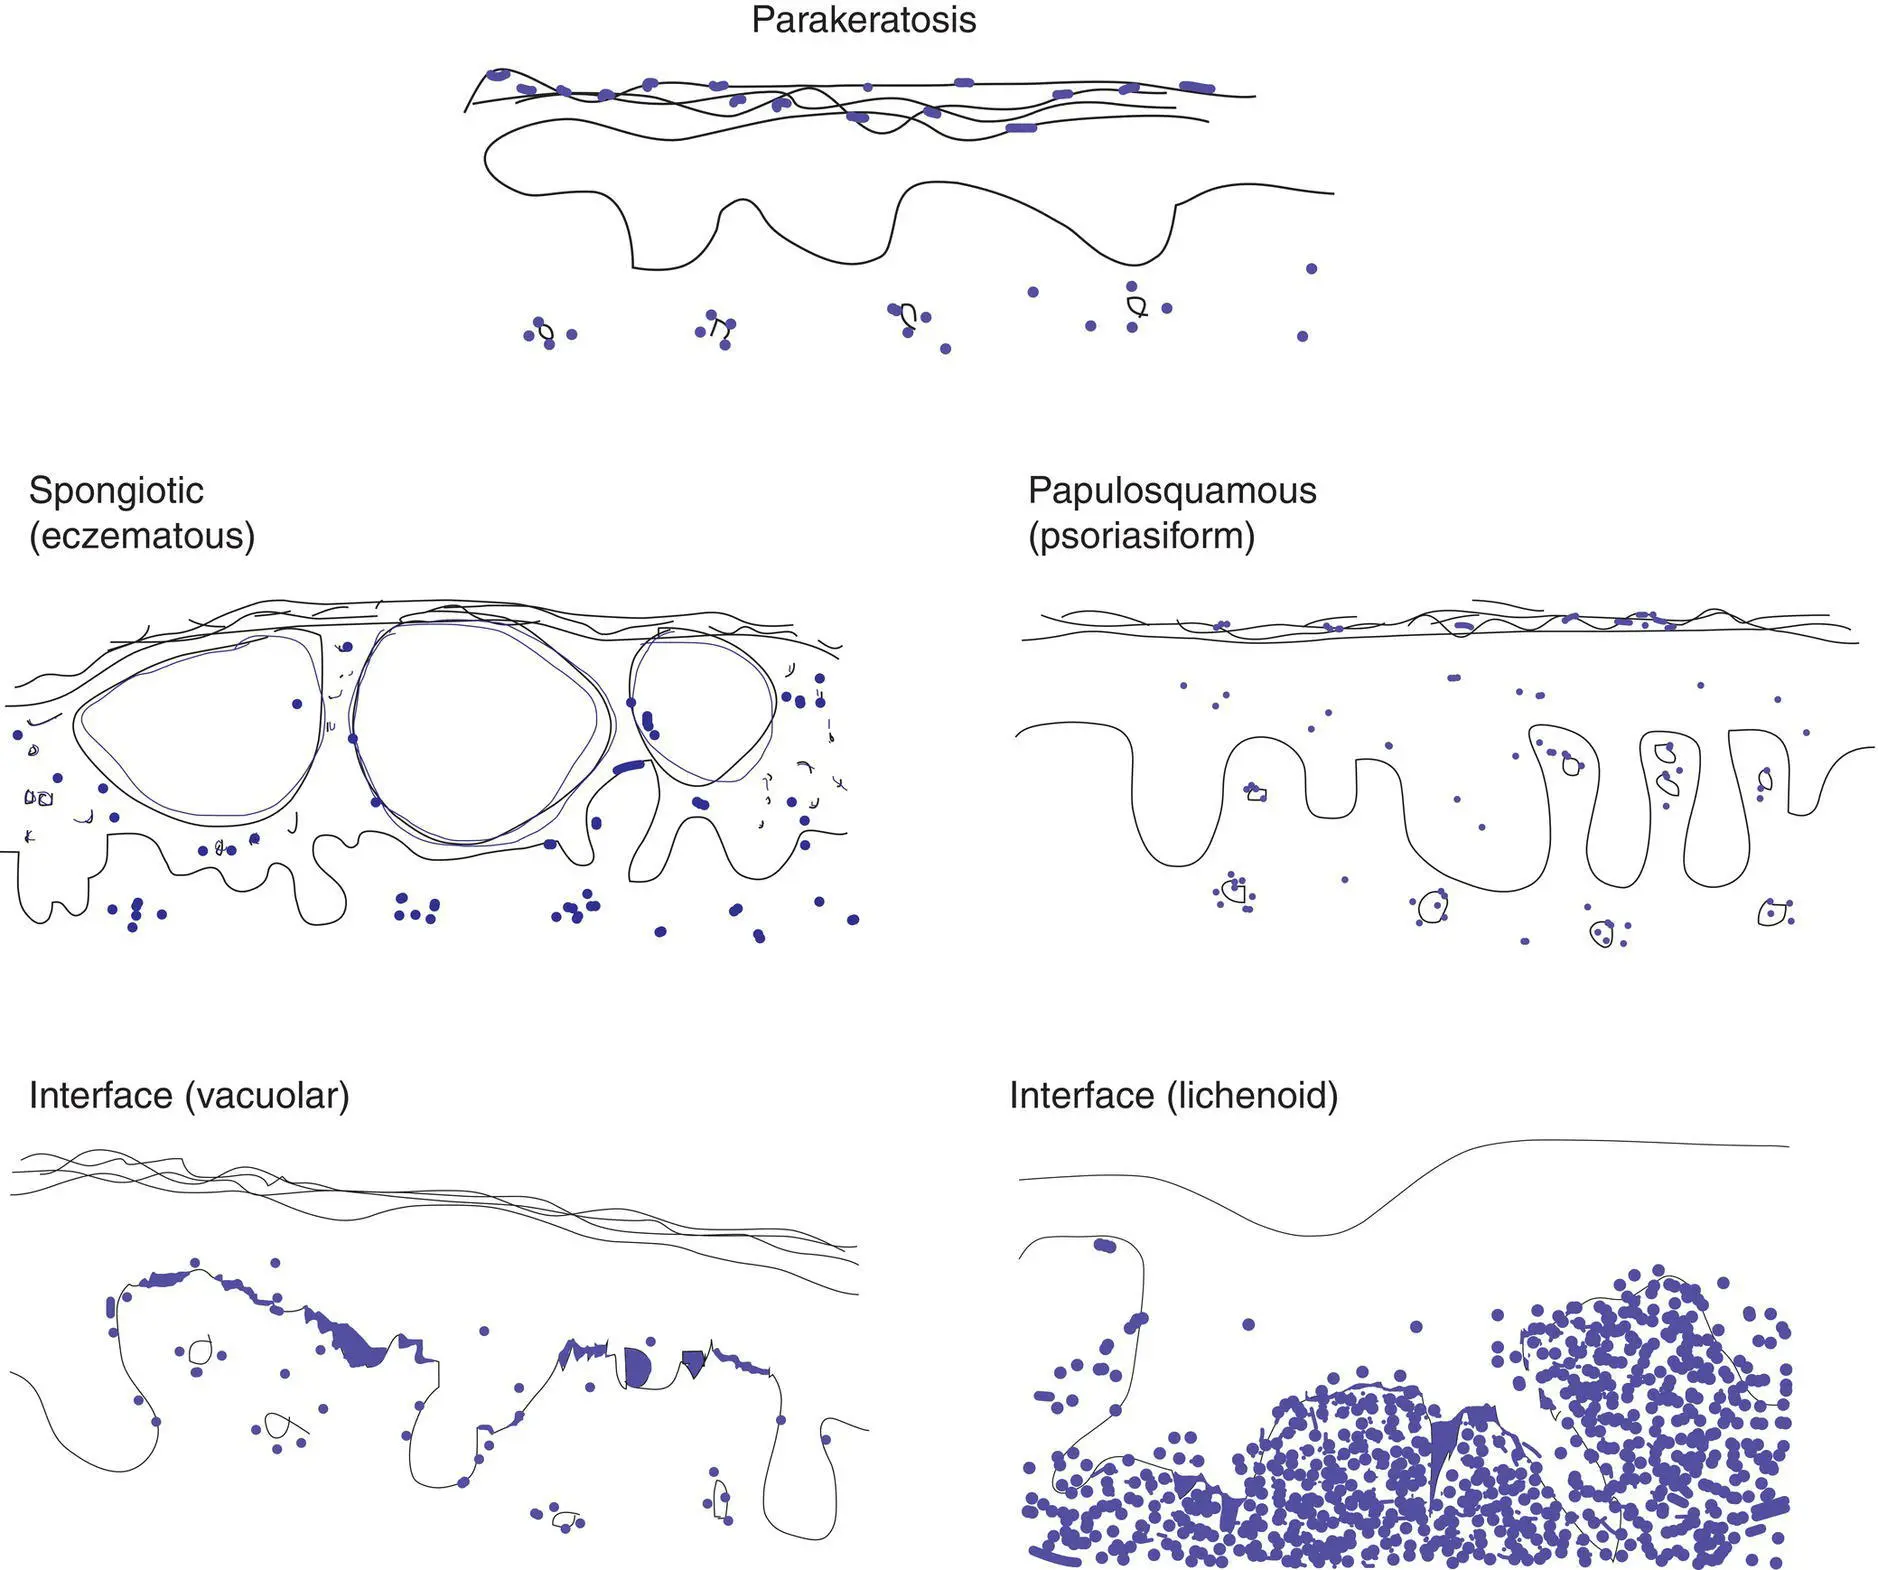

“Rash”: key concepts

The eye can be trained to focus in on the blue areas (figure–ground separation; grouping)

Key features include epidermal changes (A), distribution of inflammation (B), and inflammatory cell type (C)

Parakeratosis is often present in spongiotic and papulosquamous disorders; dry parakeratosis without serum but with neutrophils is suggestive of psoriasis

Simplistically, a dermatitis can be categorized as spongiotic, papulosquamous, or interface

Figure 3(A) Key epidermal changes

Parakeratosis: retained nuclei in the stratum corneum

Spongiosis: increased intercellular spaces and sometimes vesicles

Papulosquamous: thickened epidermis with parakeratosis

Interface (vacuolar): spaces in basal cells, which may be polygonal (squamatized), lymphocytes at junction

Interface (lichenoid): dense band of lymphocytes between epidermis and dermis with necrotic keratinocytes